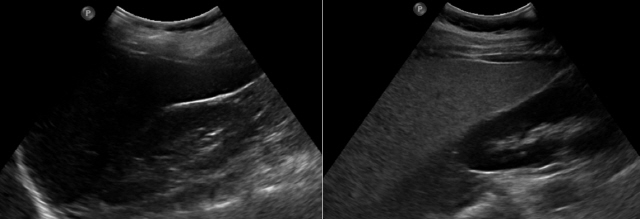

지방간은 보통 초음파검사로 확인할 수 있다. 간섬유화, 간경화 등으로 진행했는지 확인할 때는 조직 검사를 시행한다. 조직 검사는 침습적인 검사이기 때문에 비침습적인 검사로 간 섬유화도 검사, MRI(자기공명영상촬영) 등을 통해 확진하기도 한다.